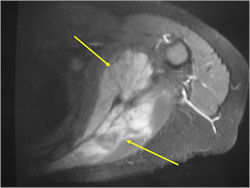

- Soft Tissue Mass in 90% of of cases

- Ewing sarcoma responds well to chemotherapy. Often there is a dramatic reduction in size of the tumor.

- Lesions grossly confined to bone have a better prognosis than those with a soft tissue component

- Tumors greater than 8cm in maximum dimension and those with greater than a volume of 100cc have been associated with a worse prognosis